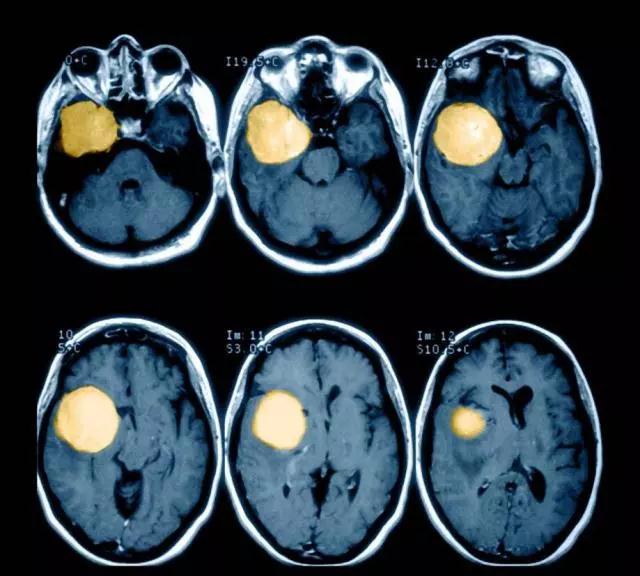

1、脑肿瘤按其起源部位可分为原发性颅内肿瘤(起源于颅内组织的肿瘤)和继发性颅内肿瘤(由身体远隔部位转移或由邻近部位延伸至颅内的肿瘤)。

2、按其生物学行为可分为良性颅内肿瘤和恶性颅内肿瘤。